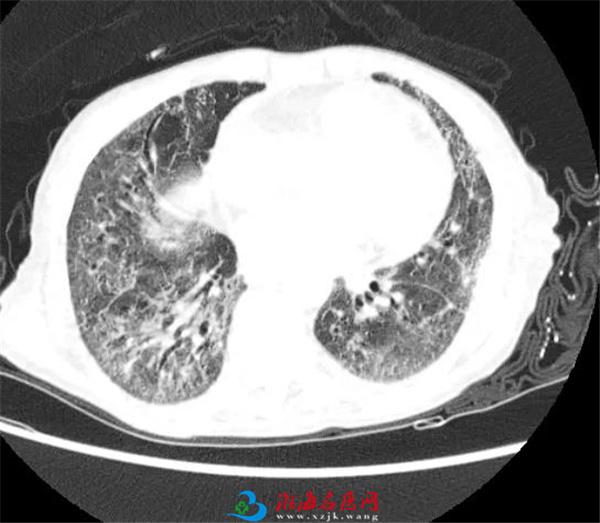

2021年05月15日徐医附院呼吸ICU急诊收治一例急性呼吸衰竭、两肺弥漫性病变的老年女性危重患者,该患者除肺部广泛病变外,同时伴有心肌酶明显升高、肝肾功能不全,考虑多脏器功能衰竭、急性心肌梗死可能。该患者既往3年曾多次因精神异常、肺部病变辗转于多家三级医院治疗,一直未得到明确诊断和有效治疗。此次入院时两肺间质病变进行性加重,出现心功能不全、肾功能不全、肝功能不全等多种并发症,病情十分危急。

各位专家听取张蕊医师汇报病史,并详细分析临床资料,科学严谨地提出诊治意见。通过各位专家综合讨论,判定该患者为多发性肌炎和干燥综合征继发的间质性肺疾病,多脏器功能不全为结缔组织病的多系统受累表现。通过一个多小时的讨论,为患者提出了综合治疗方案,包括激素、免疫抑制剂、呼吸支持、改善心功能、保肾、抗凝治疗等,同时密切随诊,积极防治继发性感染。目前该患者呼吸系统症状、心功能、肾功能、肝功能已有改善,病情趋于好转,已于5月21日康复出院。

间质性肺疾病病是以肺泡壁为主包括周围组织及其相邻支持结构的一组疾病群,该疾病谱包括200多个病种,病因主要包括已知原因(环境暴露、药物和结缔组织病等)和未知原因(特发性间质性肺炎)因素等。近年来间质性肺疾病的患病率逐年上升,已成为临床常见病,一直是呼吸系统疾病中诊断和治疗“疑点”最多、“难度”最大的一类疾病。其病因诊断和治疗极具挑战性,需要多学科合作才能得出“临床-放射-病理”精准诊断和制定个性化的治疗方案。